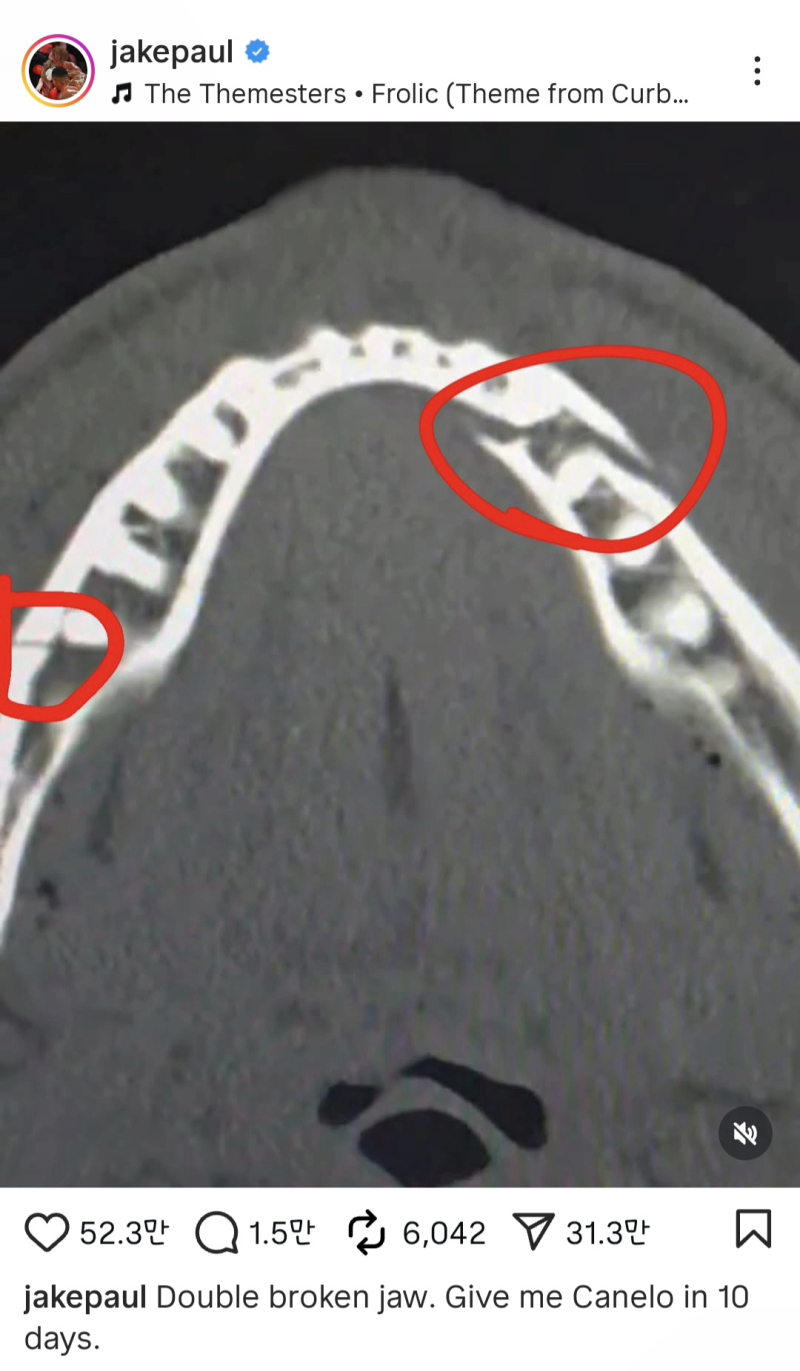

폴은 21일(한국시간) 자신의 소셜미디어(SNS)에 턱부위 엑스레이 사진을 올리며 "턱 두 곳이 골절됐다"고 밝혔다.

하지만 폴 역시 특유의 자신감을 잃지 않았다. 폴은 SNS에 "10일 뒤에 카넬로 알바레스를 데려와라(붙여달라)"고 말했다. 알바레스는 프로 복싱 전적 63승 2무 3패를 기록 중인 통합 챔피언이다.